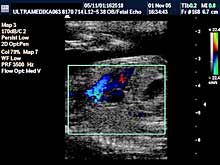

- 3D Sono CT SRCA PLODA (fetalna ehokardiografija) Prostorno, vremenska

korelacija ultrazvučnih markera prikazana multiplanarno predstavlja

dopunsku metodu u otkrivanju urođenih srčanih anomalija.

Napomena:

a)

Urođene srčane mane su 6 puta češće od hromozomskih anomalija i

njihova težina često zahteva prekid trudnoće. b)

Ovaj pregled je posebno registrovan za trudnoće koje su prethodno

imale plod sa srčanom manom ili kada u okviru standardnog pregleda

nisu dobijene sve validne ultrazvučne informacije radi pouzdanog

isključenja njihovog postojanja.

Mada je prva procena anatomije srca obavezna u I trimestru trudnoće,

konačna procena se mora završiti od 16 do kraja 24 nedelje gestacije

(6 meseci). Nakon toga procena osnovne anatomije je otežana i

rezervisana je za procenu hemodinamike srca!

Primenjena tehnika:

- Broadband 2D,

- Sono CT,

- XRes,

- Harmonik mod,

- Panorama mod,

- 3D Sono CT,

- Broadband CD,

- CPA,

- 3D CPA.